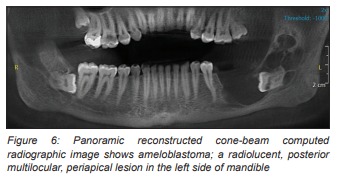

Oral Hard Tissue Lesions: A Radiographic Diagnostic Decision Tree

Oral Hard Tissue Lesions A Radiographic Diagnostic Decision Tree